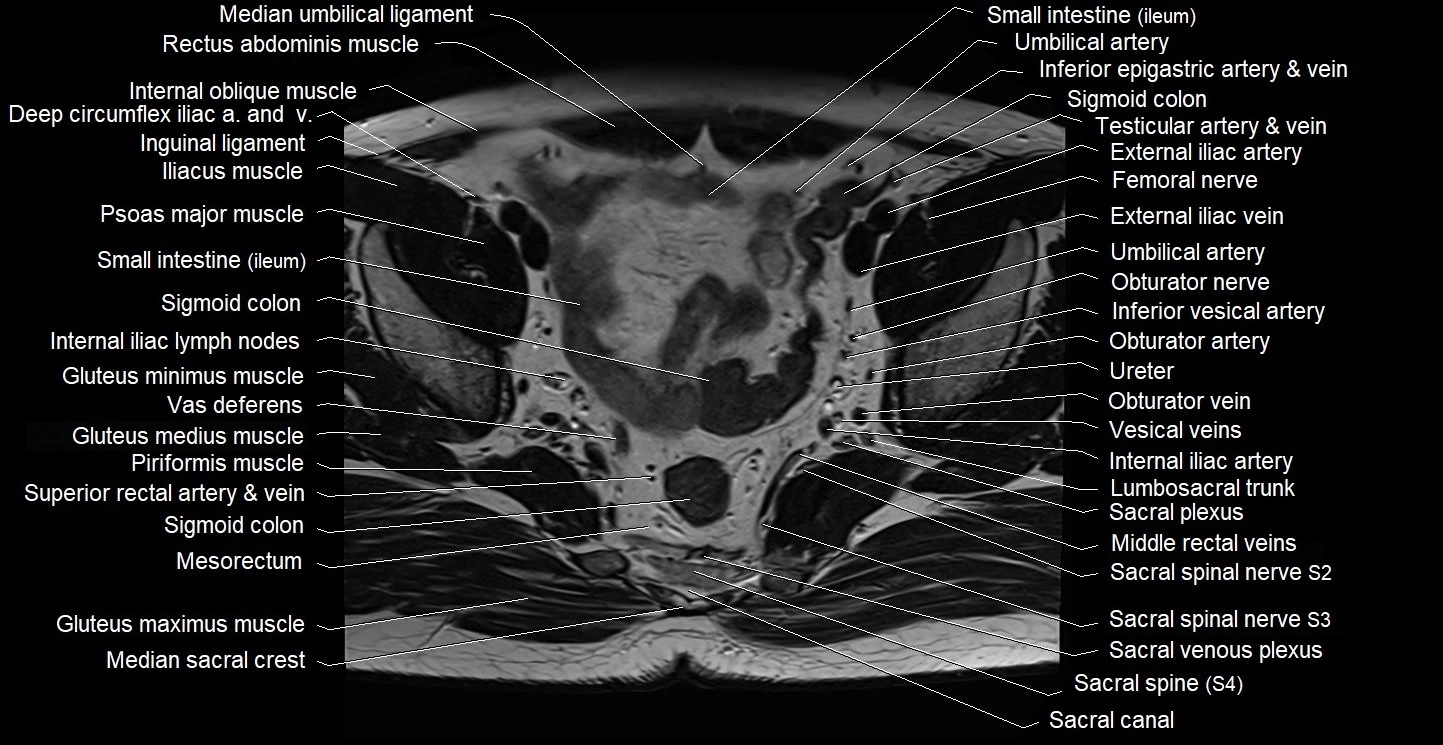

- Common iliac lymph nodes

- Deep circumflex iliac artery

- External iliac artery

- External iliac vein

- Femoral nerve

- Gluteus minimus muscle

- Iliopsoas muscle

- Inferior epigastric artery

- Inferior epigastric veins

- Inferior vesical artery

- Inguinal ligament

- Internal iliac artery

- Internal oblique muscle

- Left ureter

- Lumbosacral trunk

- Median sacral crest

- Median umbilical ligament

- Obturator artery

- Obturator nerve

- Obturator vein

- Piriformis muscle

- Psoas major muscle

- Sacral canal

- Sacral plexus

- Sigmoid colon